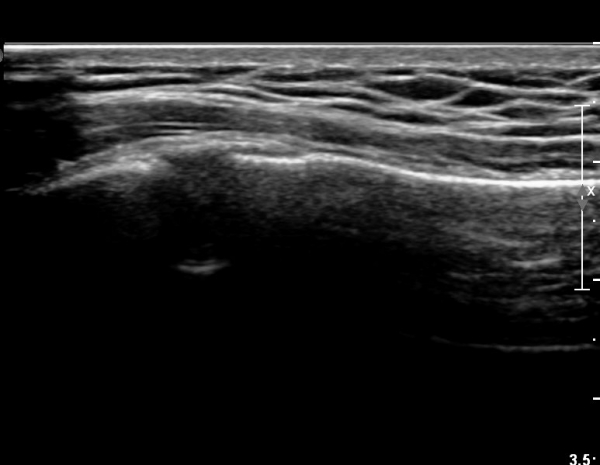

Äá¾Ë»À Á¾´Ü¸é°Ë»ç¿¡¼­ Äá¾Ë »À ±ÙÀ§ºÎÀÇ ÇÇÁú°ñ °ß¿­ÀÌ °üÂûµÊ(»çÁö 4).